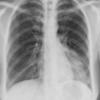

Case 2  Lingular pneum Lat

Date: 04/17/2005

Views: 7066